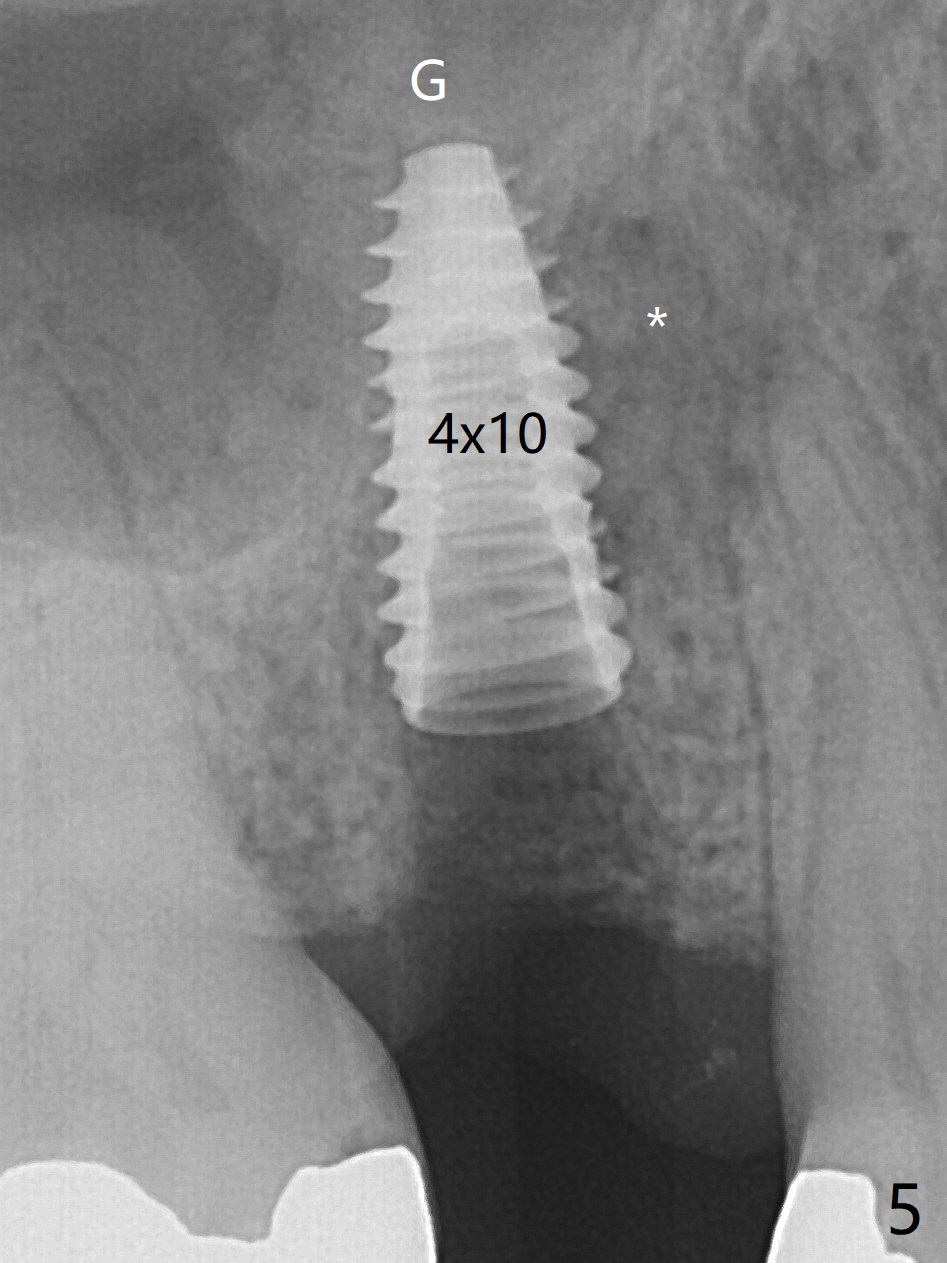

The 48-year-old man agrees to extract the tooth #4 with buccal and palatal fistulae (Fig.1,2 >) and large PARL (Fig.3 *) because of purulent discharge. The large post (Fig.3 P) is most likely associated with a longitudinal fracture. The latter is not noted until postop (Fig.4 <). Intraop finding is large amount of granulation tissue removed from the mesial apical region (Fig.3,5 *). With 10.5 mm offset, Sinus Approach Drill (19 mm) is estimated too short for sinus lift after 3x8.5 mm drill. Without careful repeated check, 2.2x10 and 2.2x11.5 mm drills are used. The sinus floor is perforated, but the membrane seems to be intact. The perforation is too small to insert PRF, but alright for allograft. Then nose blowing test shows that the sinus membrane is perforated, which seems to be repaired after placement of 2 pieces of PRF membrane, followed by another round of allograft (Fig.5 G), which is lifted by a 4x10 mm IS dummy implant. Before placement of a 4.5x11.5 mm final UF implant, allograft is placed in the 3 defective bony areas mentioned above, including the apical mesial one (Fig.6 *). But the final UF implant seems too short with non-satisfactory torque. The latter appears to be solved with the increased length of the implant (Fig.7). The gingiva around the provisional (P) is healthy without fistulae buccal (Fig.8) or palatal 17 days postop (Fig.9). A new abutment with 1 mm longer cuff is seated completely 5.5 months postop (Fig.10 < (no gap), as compared to Fig.7). The lower portion of the mesial defect seems to have been repaired (Fig.11 arrow, as compared to Fig.7). The bone in the sinus seems stable 1.5 years postop (Fig.12). There is no crestal bone loss 4 months post cementation (Fig.13). Return to Upper Premolar Immediate Implant, Trajectory II Xin Wei, DDS, PhD, MS 1st edition 09/27/2019, last revision 04/12/2021